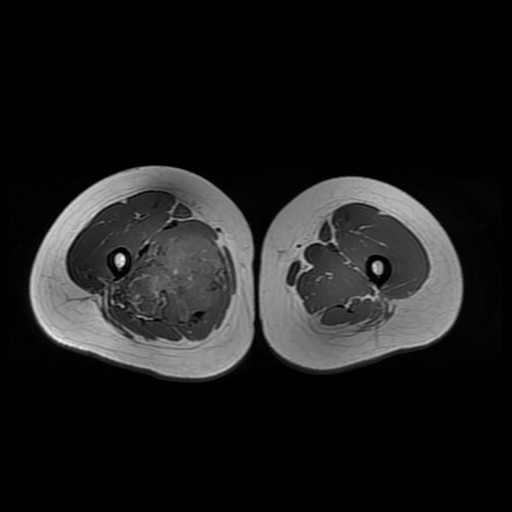

诊断:肺占位性病变(转移瘤?);大腿软组织疾患(右侧大腿肿物) 治疗:入院右下肢MR平扫+增强扫描:右侧大收肌软组织占位性病变,考虑间叶源性恶性肿瘤可能性大,血管源性可能?瘤周多发静脉曲张及侧枝循环形成,建议CT增强扫描进一步检查明确血管情况。遂于声引导下右大腿肿物穿刺活检,病理结果提示:(右大腿肿物)送检穿刺组织,肿瘤细胞形成器官样及腺泡状结构,细胞巢间为纤维性分隔,细胞呈大圆形、多边形,胞质丰富透亮,部分呈嗜伊红色,细胞核大,核分裂象少见,结合临床病史及免疫组化,考虑为腺泡状软组织肉瘤。免疫组化结果(①):CK(-),Vim(-),Ki-67(5%+),HMB45(-),MelanA(-),SMA(+),desmin(-),Myogenin(-),MyoD1(-),S100(-),NSE(部分+),CD56(-)。